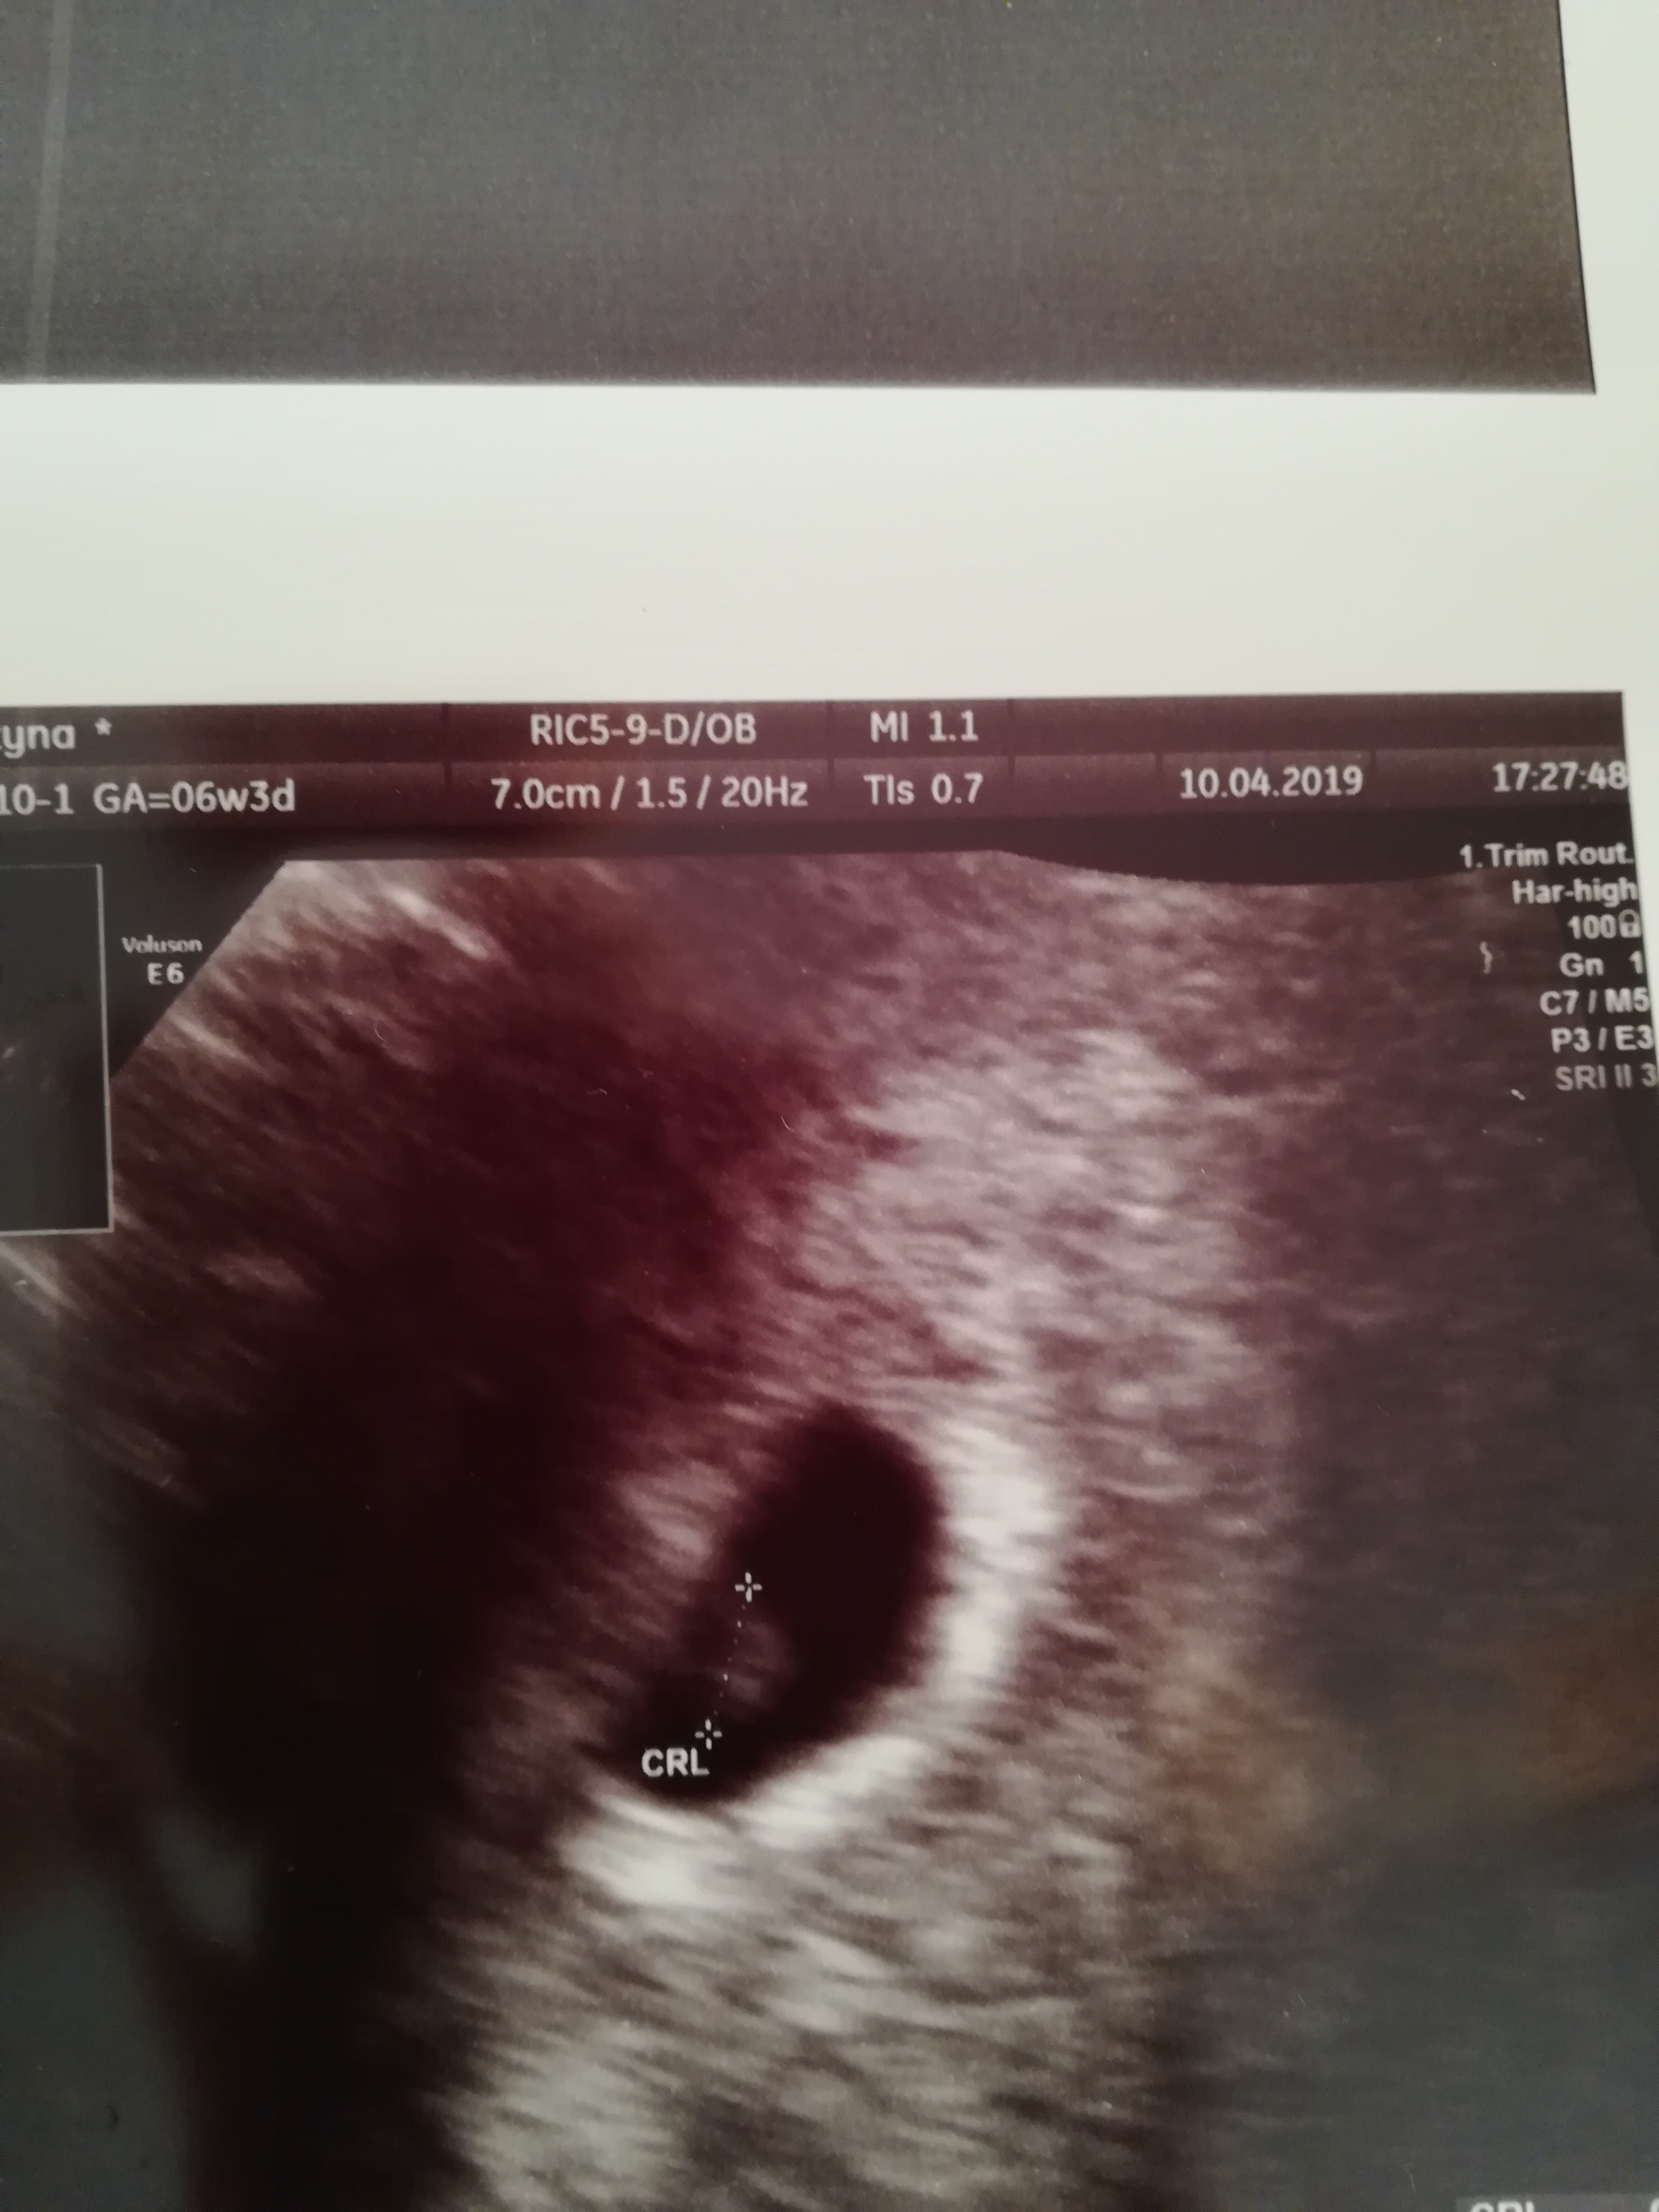

Hej kochane. Już po wizycie u gina. Wg USG ciąża młodsza o 4 dni. Jak widać zarodek jest :) kolejna wizyty za dwa tygodnie. Co do plamień, jeśli jest ich mało i nie są żywo czerwone to lekarz kazał mi się nie stresować, jedynie obserwować. Mogą być związane z tym, że mam krwiaka, ale też od infekcji. Okazało się, że luteina dowcipna, którą kazano mi przyjmować od czasu wizyty na izbie przyjęć wywołała u mnie stan zapalny. Kategorycznie mam zakaz jej używania. Zamiast tego mam brać progesteron i globulki Macmiror żeby uporać się z zapaleniem.

Załączniki

• IMG_20190410_185017.jpg

IMG_20190410_185017.jpg

1,1 MB · Wyświetleń: 106

U Ciebie to pięknie wyglada!